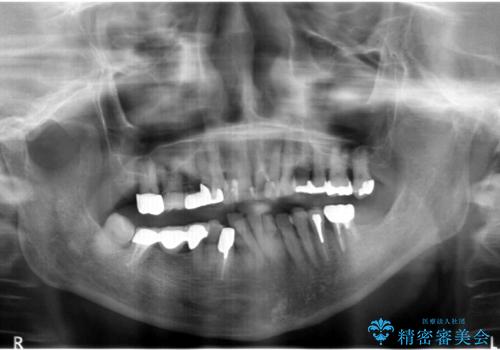

親知らずの移植 4年半経過症例 70代女性

- 親知らずの移植治療から4年半経過した患者様です。

- ¥250,000 (自家歯牙移植、根管治療、仮歯、土台、被せ物)費用は治療当時の料金となります

4年半前に行った自家歯牙移植に大変ご満足頂き、ご家族も紹介して下さいました。

自家歯牙移植は40歳以上の場合、若年者に比べ成功率が低くなるとの報告もありますが、状態によっては移植が可能な場合もあります。